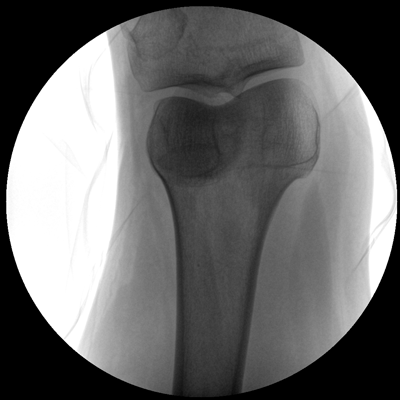

Clinical picture

臨床圖片